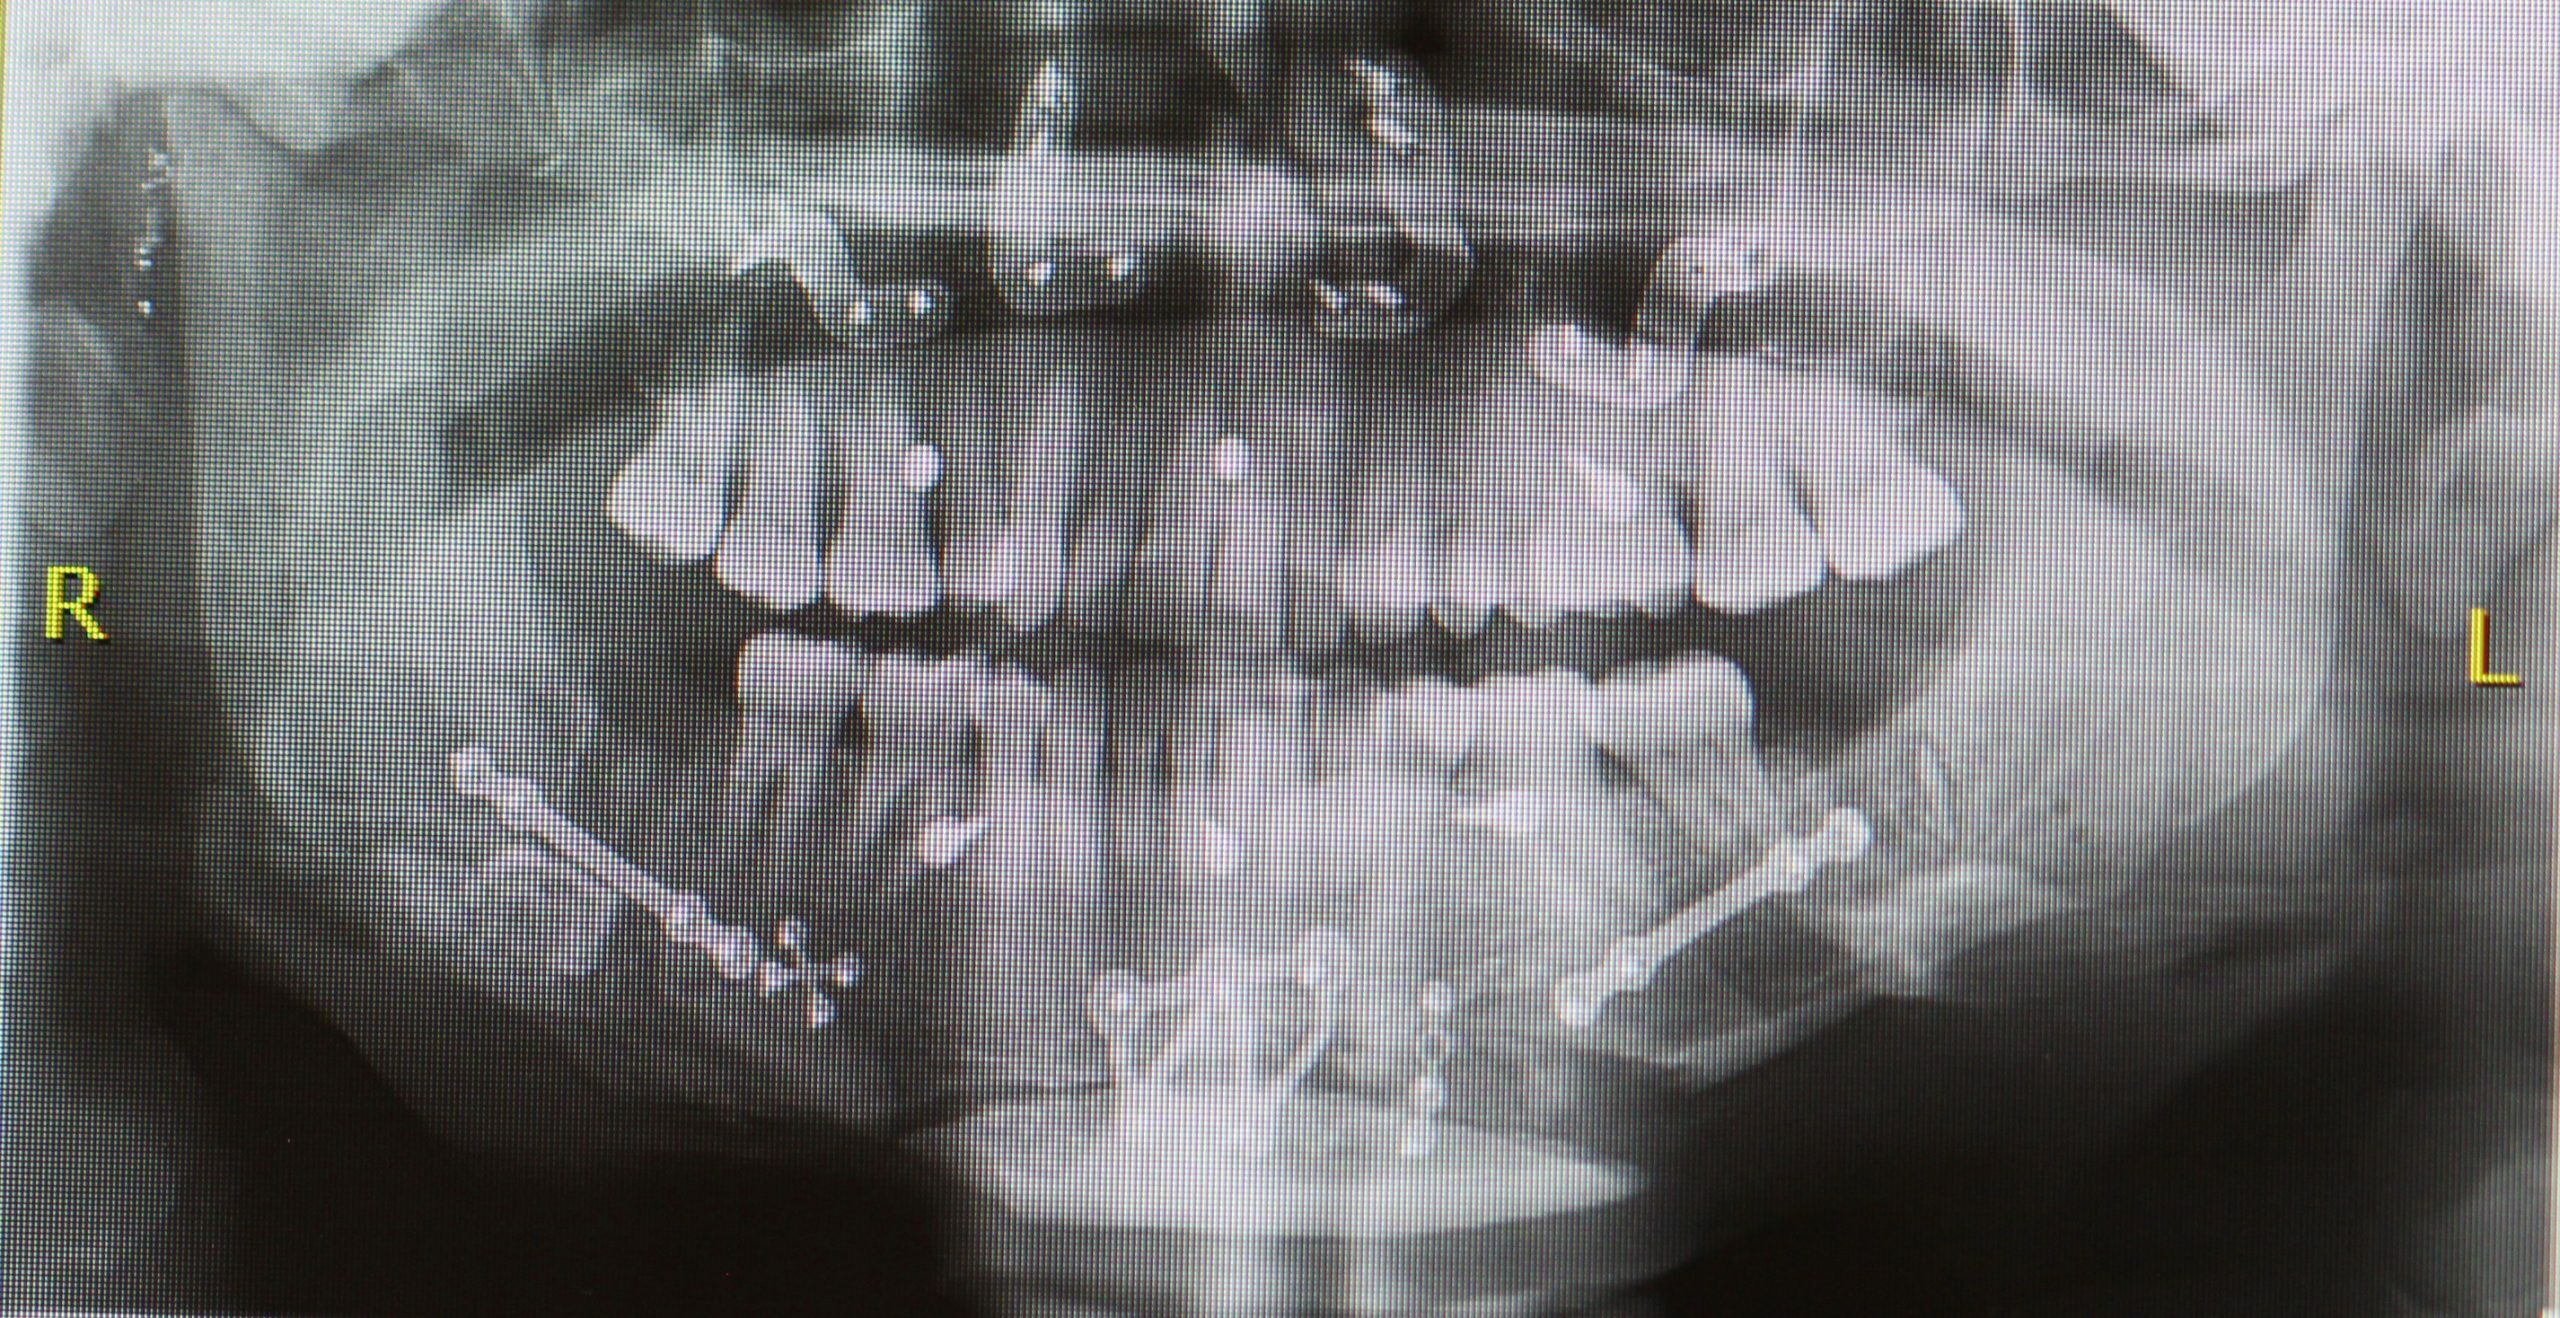

• Intervención Quirúrgica Maxilofacial: Reposicionamiento de los maxilares a la posición ideal, definida en la planificación virtual. Esto logra Armonía Facial y Mejora Funcional. El hueso movilizado se estabiliza con miniplacas de titanio.

Casos de Éxito: Transformación Integral y Calidad de Vida

Nuestros casos de éxito reflejan una mejora sustancial en la calidad de vida, optimizando la función masticatoria y logrando una armonía estética que eleva la autoconfianza.